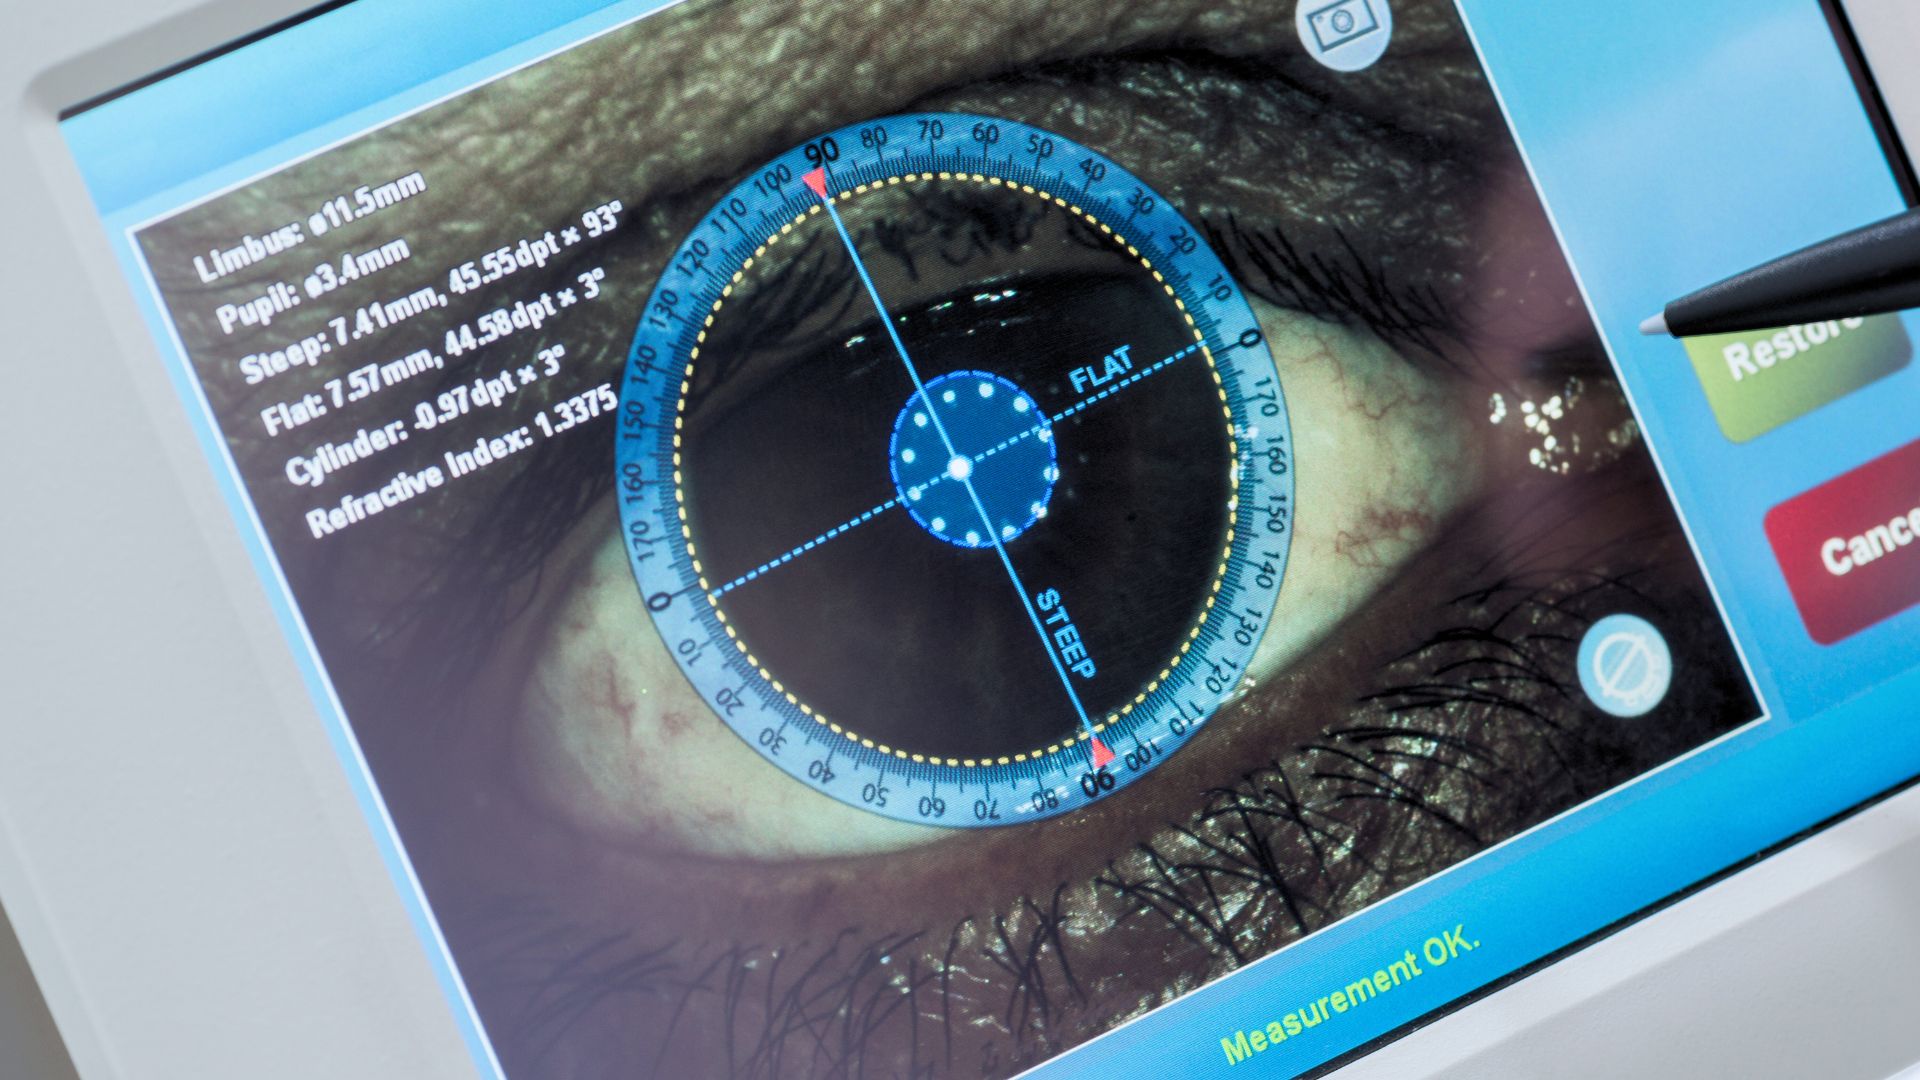

Bilan visuel, fond d’œil, dépistage du glaucome et des troubles de la vision.

Bilan visuel, fond d’œil, dépistage du glaucome et des troubles de la vision.